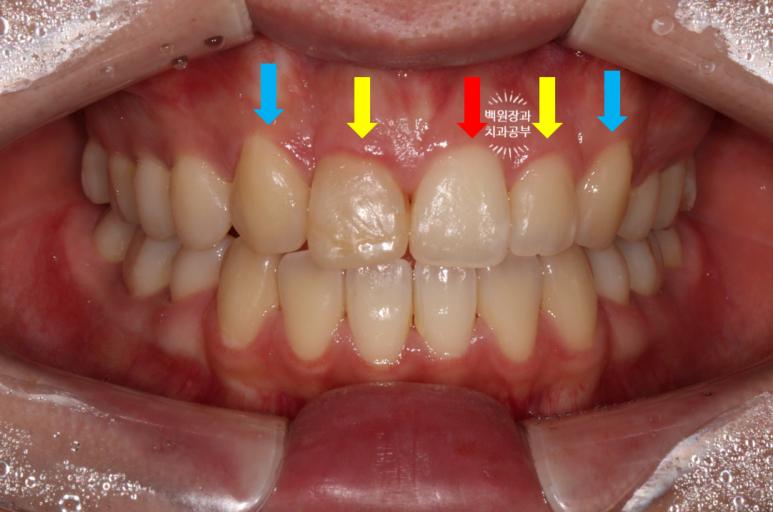

다시 보시면, 빨간색으로 표시된 것이 가장 가운데 치아인 중절치.

노란색으로 표시된 것이 작은 앞니인 측절치

파란색으로 표시된 것이 송곳니인 견치입니다.

마치, 가운데 앞니 두개가 모두 대문니 같아 보이지만, 하나는 레진으로 감싸놓은 착시 현상이라는 것!!

비교적 세모난 모양을 갖고 있는 송곳니의 위치를 파악하시고 나면, 아!!! 하고 깨달으실거에요. ㅎㅎ